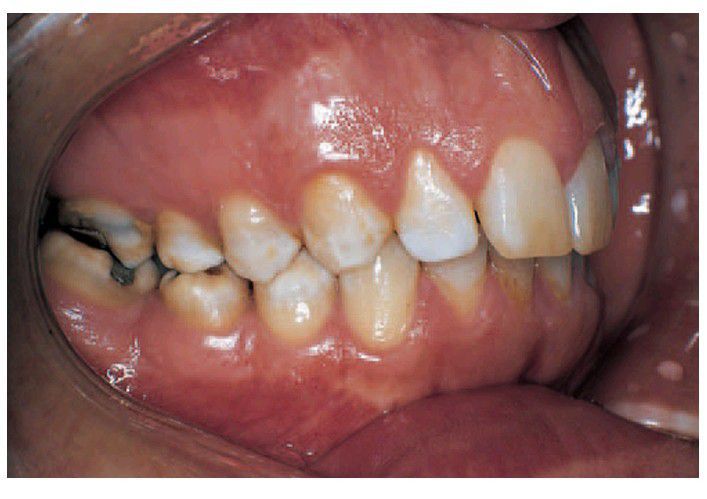

Amelogenesis imperfecta

Amelogenesis imperfecta, one of the several hypomaturation types. In this form there are opaque white fl ecks and patches affecting the occlusal half of the tooth surface.